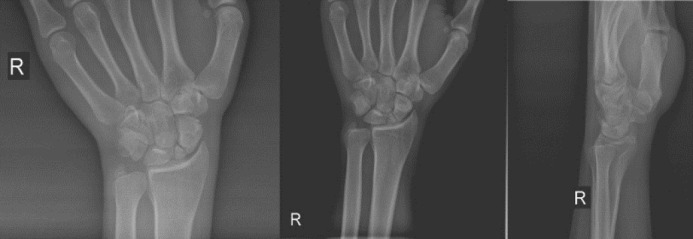

Abstract Image